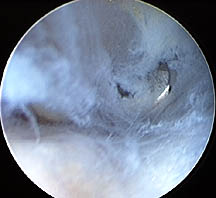

Arthroscopic Pictures of Subacromial Bursitis

Bursitis at tips of red arrows

Dense bursitis just above rotator cuff